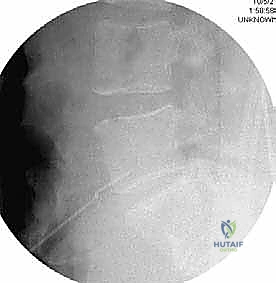

- الأشعة السينية الديناميكية (Dynamic X-rays): صور في وضعيات الانحناء للأمام والخلف لتقييم مدى عدم استقرار العمود الفقري (الانزلاق الفقري - Spondylolisthesis).

- التصوير المقطعي المحوسب (CT Scan): يقدم تفاصيل دقيقة للغاية عن البنية العظمية، وهو ضروري جداً للتخطيط الجراحي، خاصة في حالات استئصال الجسم الفقري أو وجود تعظم شديد.